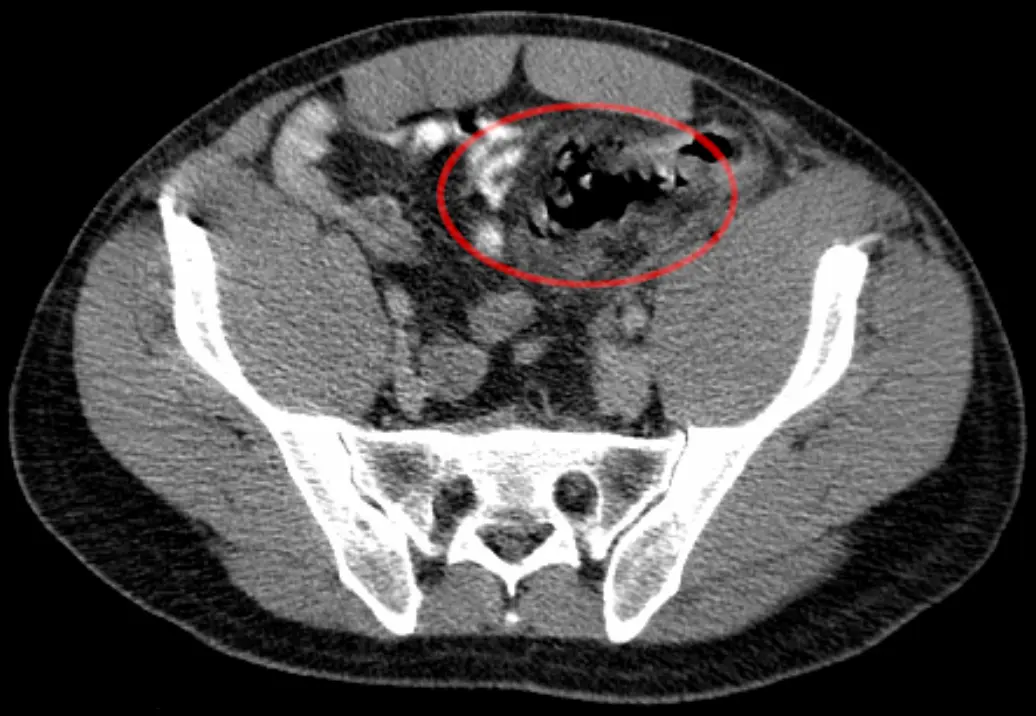

- Computertomographie (CT): Eine CT-Untersuchung kann den Darm genauer darstellen und die Ursache des Darmdurchbruchs identifizieren.